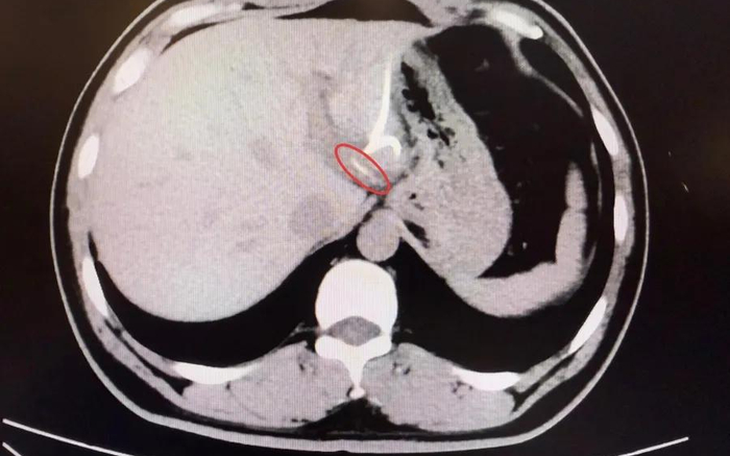

Mãi đến khi chụp CT, các bác sĩ mới phát hiện một vật thể dài, nhọn trong gan trái, gần vùng nối với dạ dày, hình dạng giống hệt… một chiếc xương cá! Hóa ra, chiếc xương này đã xuyên qua thành dạ dày, “chui” thẳng vào gan, gây nhiễm trùng và tạo ổ mủ lớn.

Sau hơn 3 tiếng đồng hồ, các bác sĩ đã tìm thấy chiếc xương cá dài 3,5cm, sắc nhọn như kim, cắm sâu trong gan trái. Sau ca mổ, anh Lý hồi phục tốt, nhiệt độ cơ thể trở lại bình thường, ổ áp xe dần tiêu biến và quan trọng hơn cả, anh giữ được nguyên vẹn lá gan của mình.